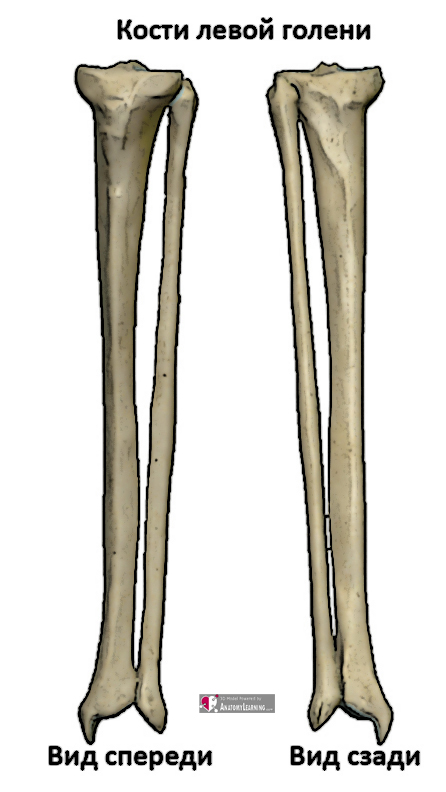

Анатомия фибулы: Подробные фотографии и схемы